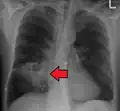

Lung abscesses are often on one side and single involving posterior segments of the upper lobes and the apical segments of the lower lobes as these areas are gravity dependent when lying down. Presence of air-fluid levels implies rupture into the bronchial tree or rarely growth of gas forming organism.

Pulmonary abscess on CXR -